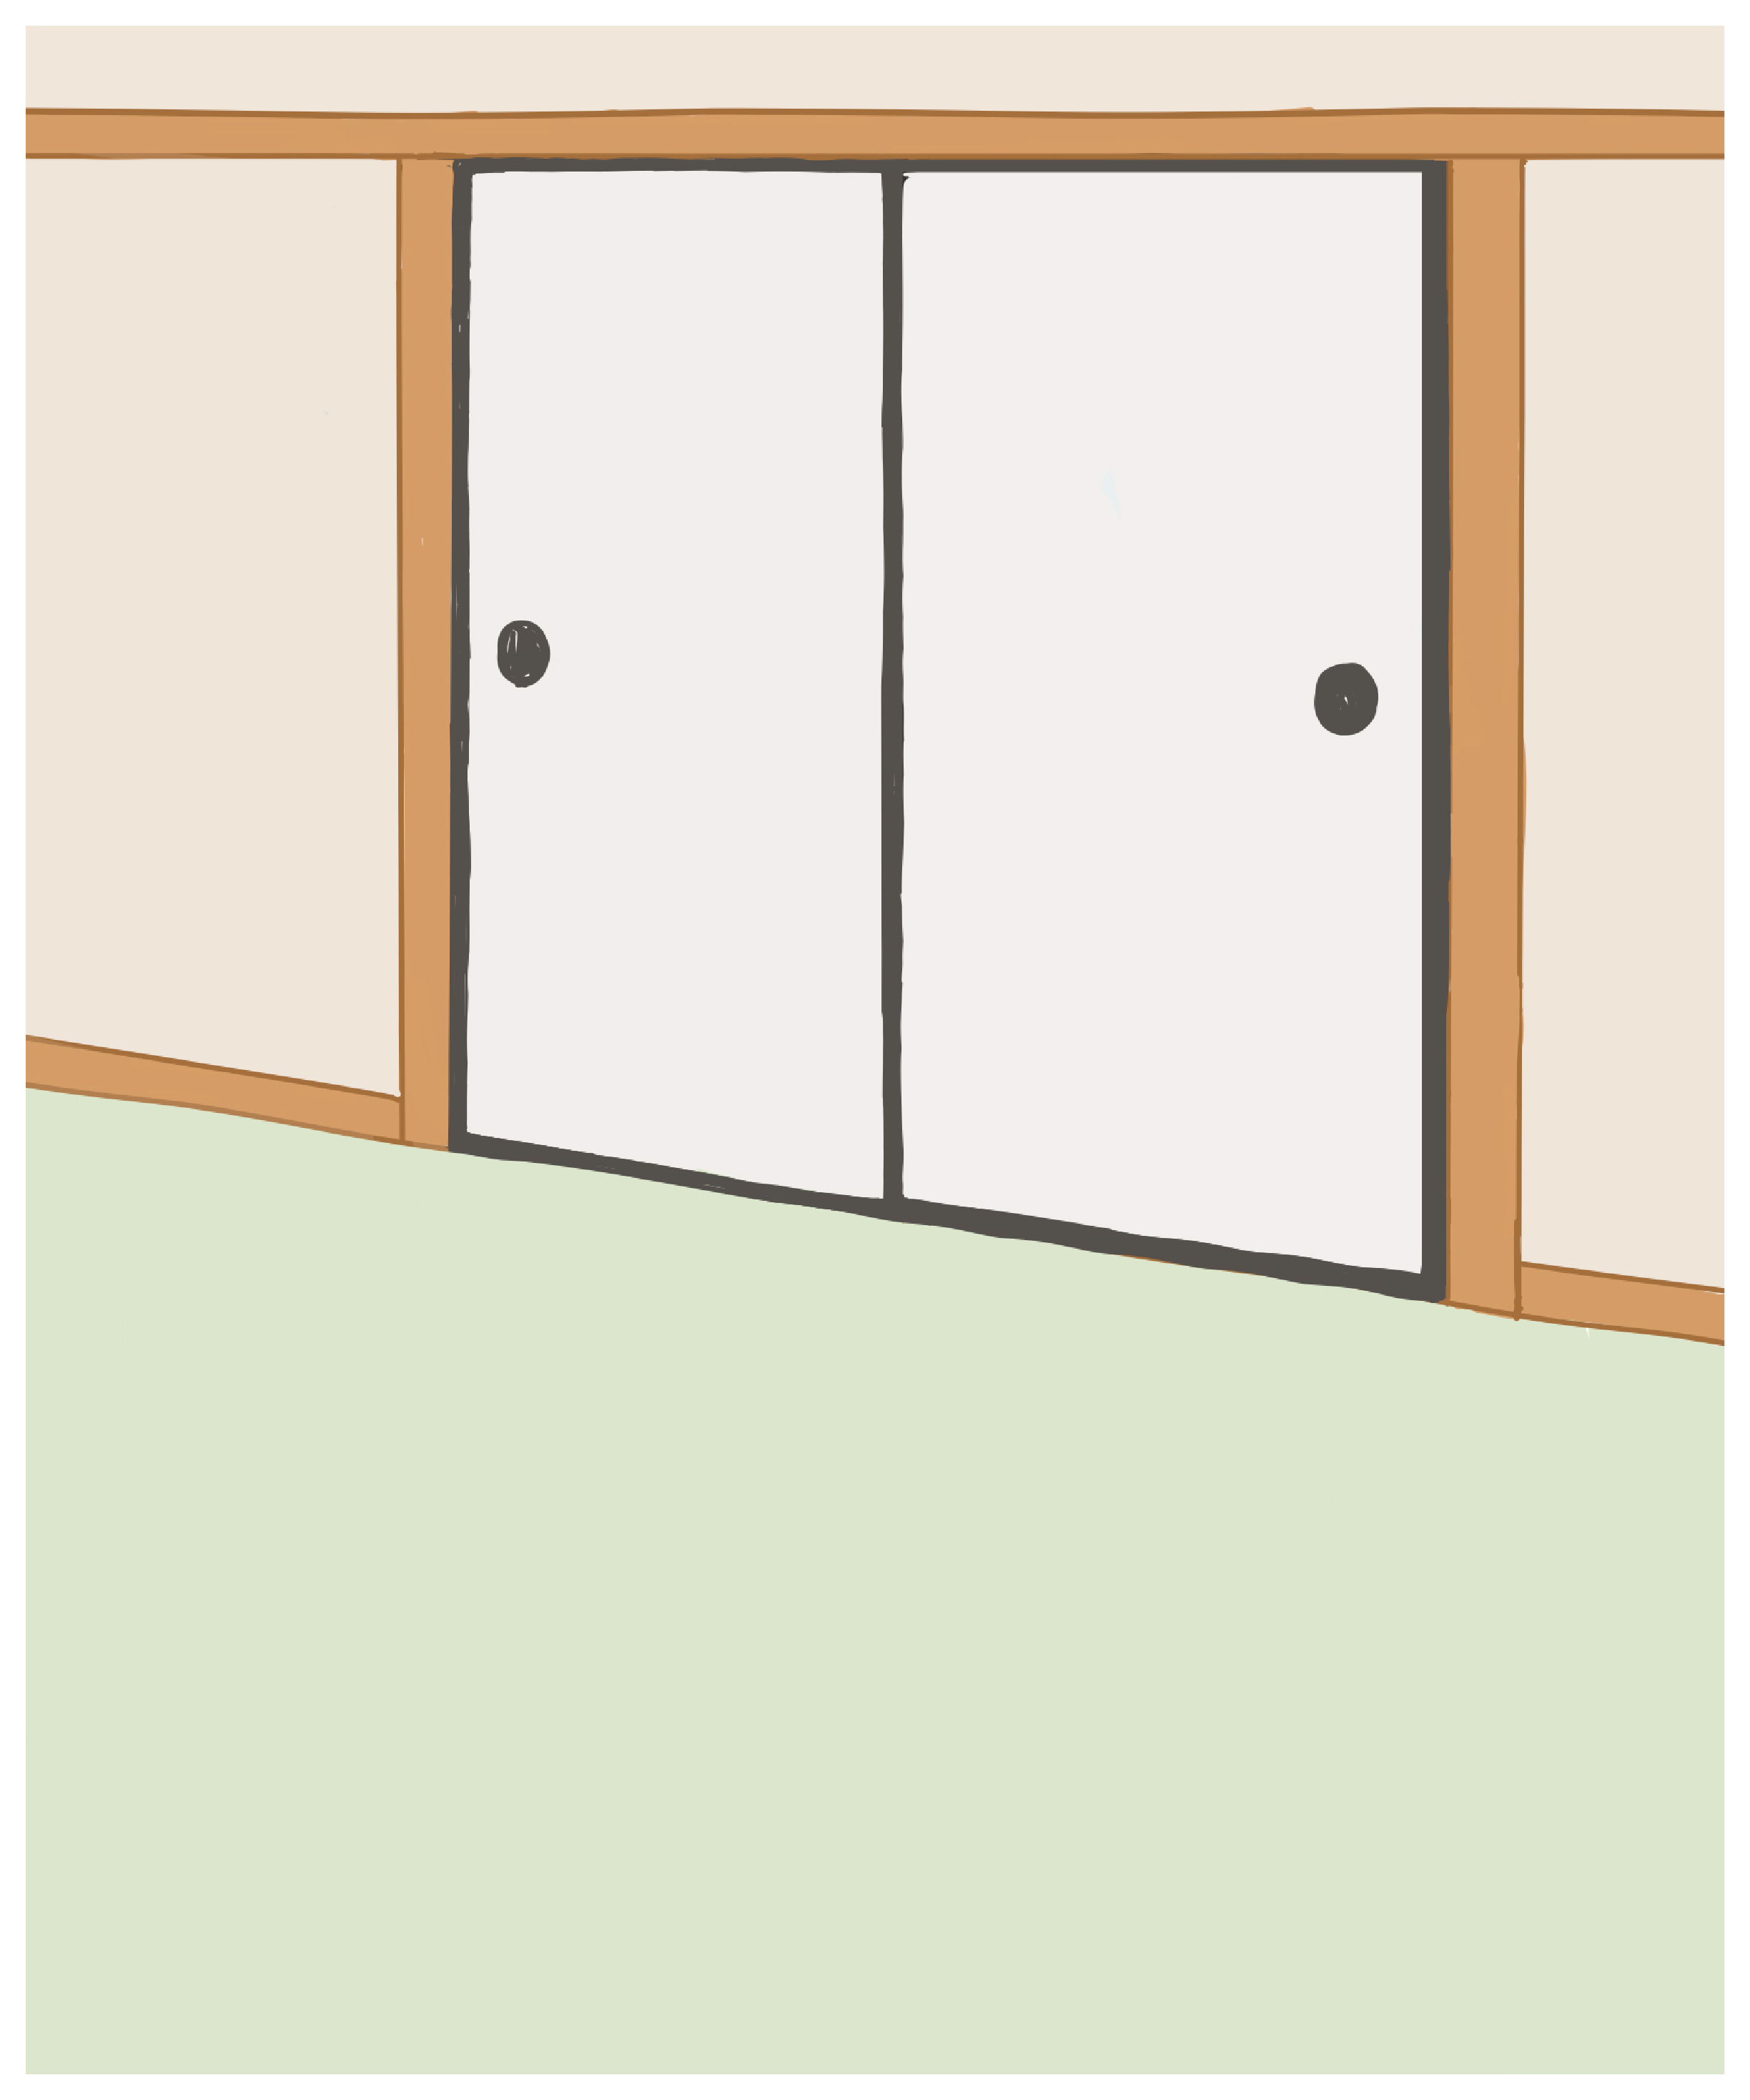

これは押し入れに綺麗に布団が入っている状態に例えると、眼窩骨折では襖が倒れ布団が外に飛び出している状態と言えます。

押し入れの中にある布団で例えると

-

1.正常時

-

2.綺麗に整頓されている

-

3.布団が外へ飛び出す

-

4.眼窩骨折の状態

-

5.眼窩骨折の治療